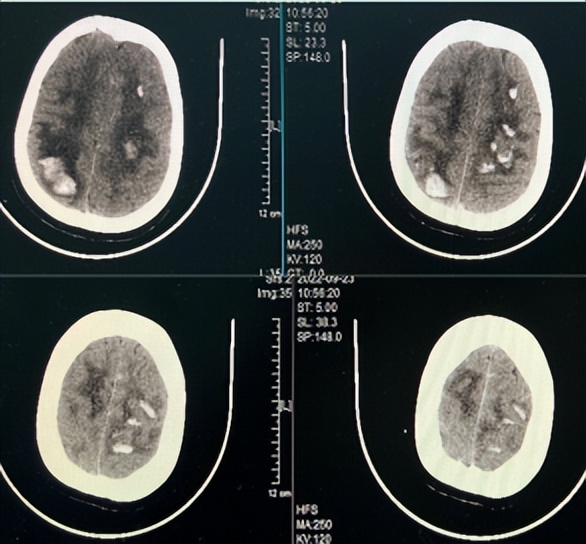

9月20日早晨,张女士突发意识不清,伴四肢抽搐、口吐白沫、小便*禁失**,持续5分钟后缓解。就诊当地医院查颅脑CT示“颅内多发出血,上矢状窦高密度影”,期间再发意识不清及四肢抽搐,持续10分钟后,抽搐停止,但是患者出现神志朦胧,肢体肌力下降,转诊我院急诊。

通过询问张女士家人,才知道她已经3次妊娠,都伴有血小板减少,至今血小板仍未恢复正常。急诊神经内科医生结合病情及颅脑CT的表现,第一时间做出了“颅内静脉窦血栓”的判断,同时联系磁共振静脉造影明确了诊断。然而,病魔还在牢牢地揪着她不放,3小时后她的意识障碍继续加重,并出现四肢无力,复查颅脑CT发现,她脑内的出血在不断增加。继而四肢抽搐,意识不清,生命危在旦夕。

▲颅内多发血肿伴水肿